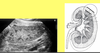

What are the Renal contours when imaged?

Smooth outer contours surrounded by reflected echoes of Perirenal fat. Renal parenchyma surrounds the fatty central renal sinus which contains the calyces infundibula pelvis vessels and lymphatics

What two parts of the kidney make up the renal Parenchyma?

The renal sinus to the outer renal surface

how can you tell this is a pediatric kidney?

the prominence of the medullary pyramids and the lack of prominence of the renal sinus as compared to the adult kidneys. (adult below)

What are the columns number Bertin?

The band of cortical tissue separating the hypo echoing medullary pyramids from the echogenic cortex